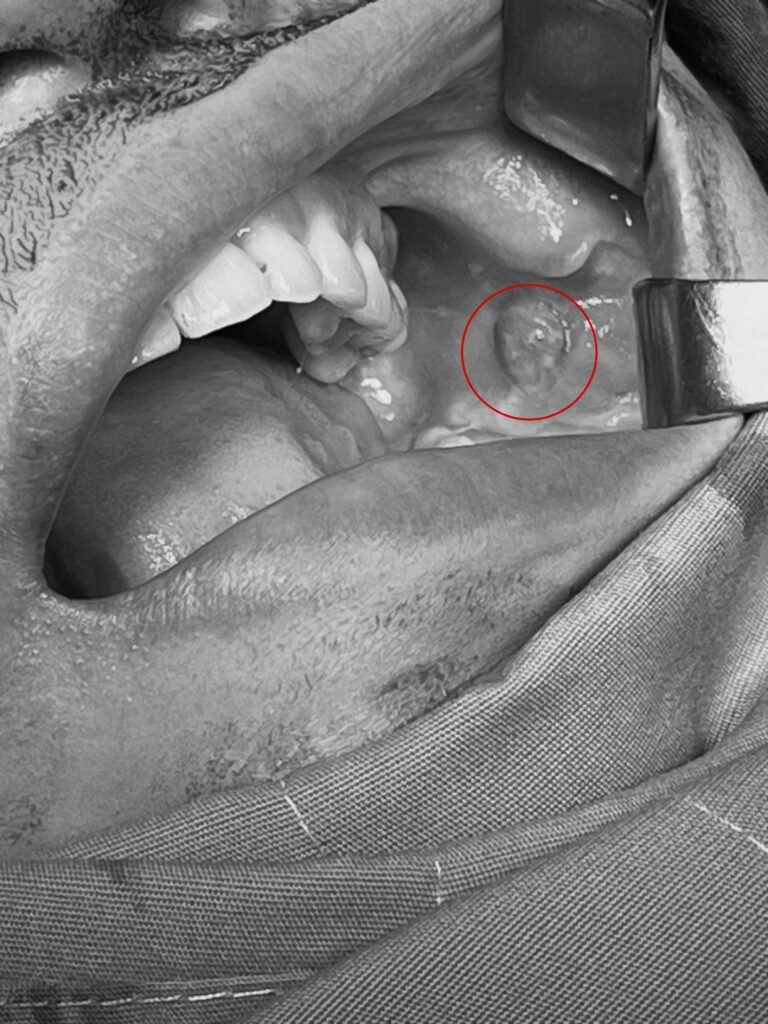

Một người bệnh 51 tuổi ở huyện Cờ Đỏ, Tp. Cần Thơ vừa được các bác sĩ Khoa Tiêu hóa, Bệnh viện Hoàn Mỹ Cửu Long gắp thành công dị vật là xương cá đâm thủng dạ dày. Trước đó, bà N. T. H cảm thấy đau bụng nhiều phần trên rốn sau khi ăn […]